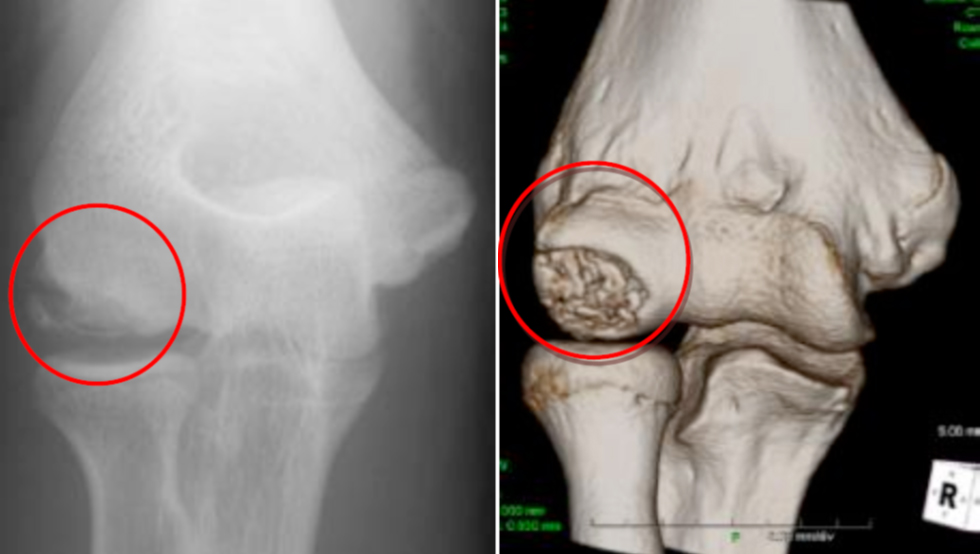

【図1 :MRI・CTでみえる離断性骨軟骨炎(左:MRI、右:CT)】

離断性骨軟骨炎は成長期に生じやすく、軟骨が骨ごと剥がれてしまう障害です。またこの他に軟骨損傷の病態は様々で、離断性骨軟骨炎の他に、靭帯損傷に伴う損傷、膝蓋骨と言われる膝のお皿の脱臼に伴う損傷、外傷やスポーツ活動などでの過度な負荷により生じる損傷などもあります。

診断には、症状の経過や診察時の医師による徒手検査などによる他の疾患との鑑別、また画像としてMRIやCTなどが用いられます(図1)。